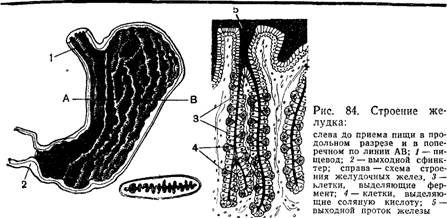

Желудок человека (рис. 84), растягиваясь, может вмещать 2—3 л воды. В его стенке находится толстый слой мышечных волокон. При их сокращении объем желудка. значительно уменьшается Слизистая оболочка желудка образует многочисленные складки. что способствует лучшему соприкосновению пищи со стенками желудка. При растяжении желудка складки расправляются.

На границе между пищеводом и желудком расположена силь-ная кольцевая мышца. Сокращаясь, она запирает вход в желудок, ' и ПНща не мижет вернуться обратно в пищевод. Другая такая же кольцевая мышца запирает выход из желудка. Когда она расслабляется, пища проходит в кишечник.

Около 5 млн^ маленьких желез, расположенных в слизистой оболочке желудка, выделяют за сутки около 2 л желудочного сока. Он содержит соляную кислоту и фермент пепсин, под влиянием кото-рого начинается переваривание белков. Присутствие кислоты необ-ходимо для действия этого фе. рментя - - Кроме того, кислота играет защитнукг-р"оль7 губительно действуя на большинство микробов, попадающих с пищей в желудок.